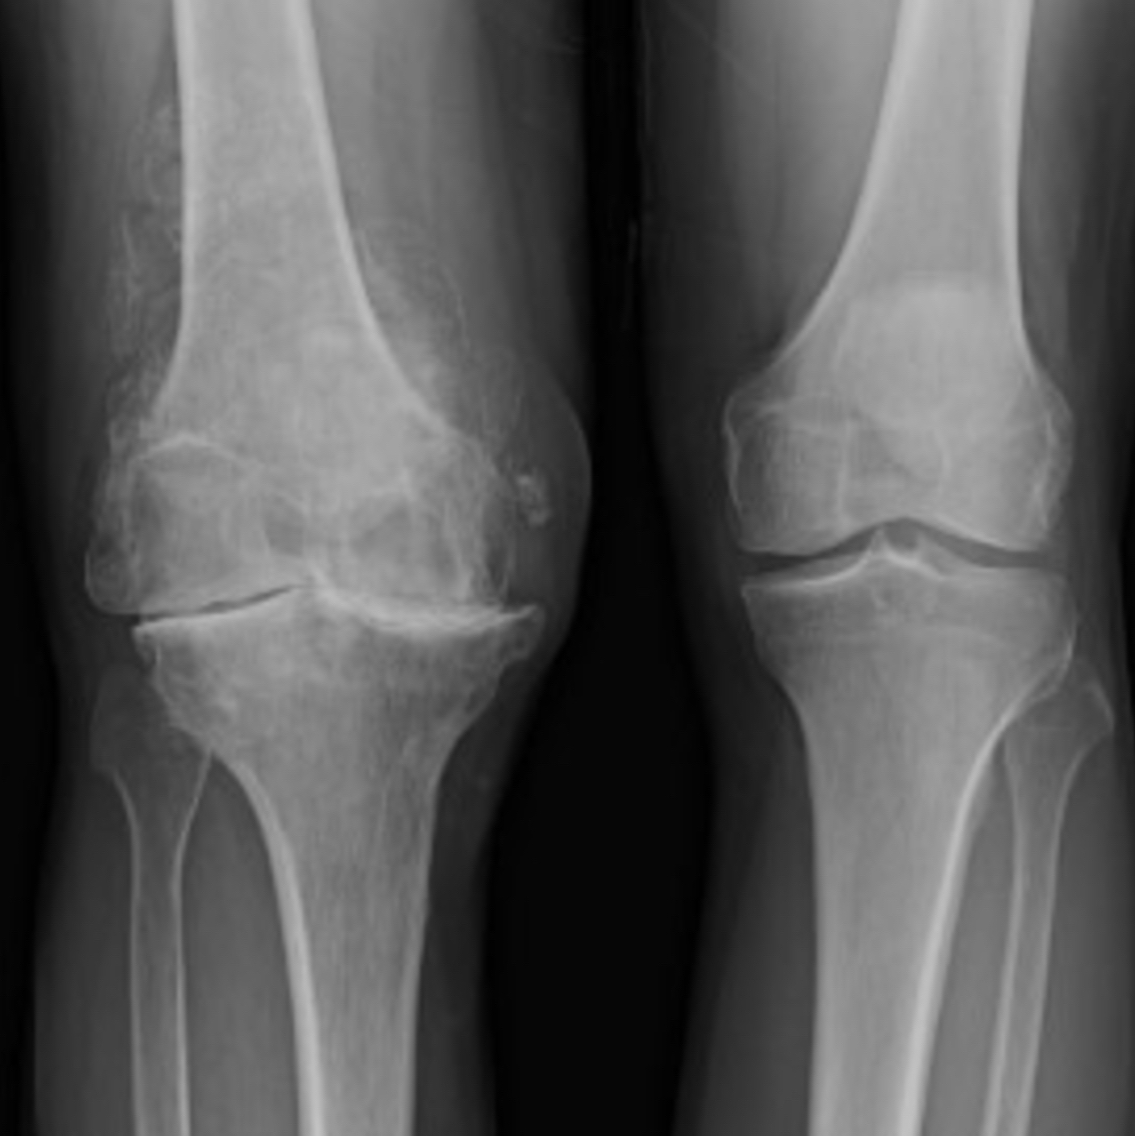

Reading X-Rays

The articular cartilage and meniscus cannot be seen on an X-ray image. An X-ray of a healthy knee with good cartilage should show a gap between the bones, such as the knee on the right of this image.

You can see that there is no gap between the bones of the knee on the left of the image. This indicates the articular cartilage and meniscus have completely worn away causing arthritis and the ends of the bones to rub. This is a painful condition.

This X-ray shows cartilage wear in the medial compartment, or inside-knee, only. This kind of uneven wear can give the patient the appearance of being ‘bowlegged’ over time as the medial joint space collapses.

Wear on the outside or lateral compartment only can bring about the reverse appearance of having ‘knock knees’.